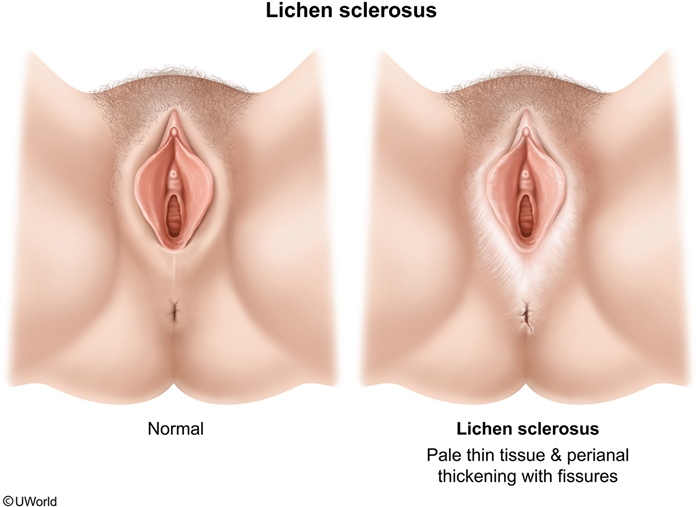

lichen sclerosus presents in ___ and __ populations as they are _

young (prepubertal) and old (postmenopausal) vulva-havers, as they are low estrogen